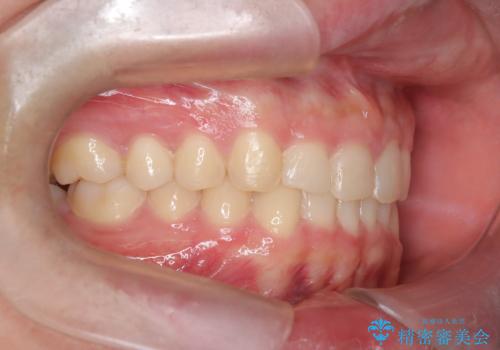

【インビザライン】前歯のガタガタと、前歯の噛み合わせが深いことを治したい。

- 前歯のガタガタと、前歯の噛み合わせが深いことを治したい。との主訴で来院されました。

シミュレーションを用いながら患者様と仕上がりについて相談しインビザラインにて治療を行いました。

仕上げは追加アライナーを数回利用しておこないました。